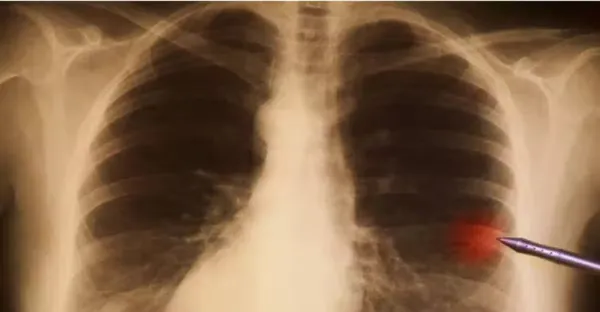

不抽菸不喝酒!45歲女確診「晚期肺癌」只因長期在做兩件事 5類高危人群要重視「早期癥狀」